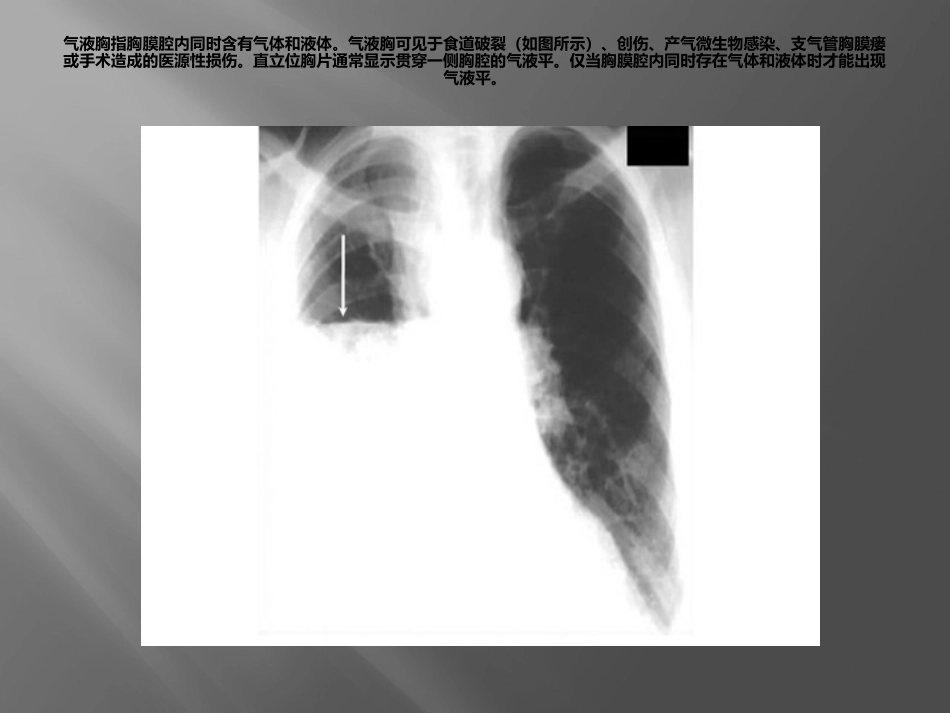

急诊常见X线表现左心室动脉瘤是心肌梗塞后的少见并发症,由于薄弱的左心室心肌组织明显突出形成。胸片显示心脏增大且心脏左缘突出。在侧位胸片中,根据动脉瘤部位的不同,可以表现为心脏前壁或后壁变形。某些病例可出现钙化线勾勒出动脉瘤外缘。气液胸指胸膜腔内同时含有气体和液体。气液胸可见于食道破裂(如图所示)、创伤、产气微生物感染、支气管胸膜瘘或手术造成的医源性损伤。直立位胸片通常显示贯穿一侧胸腔的气液平。仅当胸膜腔内同时存在气体和液体时才能出现气液平。置气管插管后,最初通过双肺听诊以及CO2监测确定插管位置,但是常规需要拍摄胸片进行确认。气管插管内嵌有不透X光的线条,以便确认位置。插管尖端应当在隆突(折线)上2-6cm(箭头)。插管尖端位于这一位置时,可以在颈部屈曲或伸展时仍保证通气充分。如果插管位置过深,则可能造成选择性单肺插管,导致对侧肺完全不张。肺不张指因肺泡塌陷导致的部分肺或全肺容积减少。肺不张的原因包括肺泡内气体被吸收后造成的阻塞性肺不张,以及由于压迫、表面活性物质缺乏、肺实质形成瘢痕或胸膜脏层和壁层不再接触造成的非阻塞性肺不张。根据受累部位和程度不同,胸片表现存在很大差异。肺叶塌陷可以表现为叶间裂移位,塌陷肺叶部位致密影,以及纵隔向同侧移位,肋间隙变窄,膈肌升高和胸腔容积减少。心脏附近肺叶不张可以使得胸片上心脏边界不清。上图所示右中叶不张,并造成心脏右缘边界不清肺栓塞指肺动脉血流受阻。肺栓塞的临床表现各异,因此准确诊断非常困难。尽管CT血管造影以及通气灌注扫描通常用于确诊肺动脉栓塞,但胸片也可能存在多种征象。Westermark征指肺血管扩张且突然中断。Hampton驼峰为肺梗死和不张引起的周边肺组织的楔形实变(如箭头所示)。胸片还可见少量胸腔积液及膈肌抬高。值得注意的是,多数情况下肺栓塞患者胸片正常。连枷胸为至少3根肋骨2处或多处骨折造成胸壁节段的矛盾运动。在吸气相,由于受到胸腔内负压的影响,受累节段回缩。连枷胸通常见于胸部严重钝性创伤患者。根据胸片评估肋骨骨折可能非常困难,有时需要拍摄多角度斜位片,并密切关注细节。上图为胸片的放大影像,显示由箭头所示肋骨骨折造成的连枷胸。如果怀疑骨折但未得到胸片确诊,可能需要进行CT扫描。吸入性肺炎是口咽部细菌或胃内容物吸入肺内导致的感染。吸入性肺炎与吸入性肺泡炎不同,后者由吸入物的直接化学损伤导致。胸片典型表现为双侧中下肺区域的致密影(如图所示)。急性期可出现一过性浸润影或肺叶实变,而慢性误吸可表现为团块影。充血性心力衰竭是一种临床综合征,指患者心脏泵出的血不能满足组织代谢需要。胸片可出现多种典型的表现。其一为心脏增大,后前位胸片显示心胸比例增加超过50%(白线)。肺组织周边可出现KerleyB线,为小叶间隔增厚的结果。胸水增多可使肋膈角变钝(红色箭头)或导致大量胸腔积液。肺水肿可以造成双侧肺纹理增加,并呈肺门周围或蝙蝠翅状分布。肺毛细血管压增加导致上叶血管直径与下叶血管相等或更粗,即头侧化(cephalization)。膈疝即膈肌缺损导致腹腔内容物进入胸腔内。多数情况下膈肌缺损发生在左侧,其原因可能与左侧膈肌较为薄弱或肝脏的保护作用有关。胸片可见双侧膈肌不对称,或膈肌水平改变(箭头)。胸腔内出现充气气管或鼻胃管有助于确诊。腹腔实质脏器一旦疝入胸腔,则表现为蘑菇形均质致密影。膈肌麻痹或肺减容手术后患者可能误诊。胸主动脉瘤指超过正常升主动脉、主动脉弓或降主动脉直径50%的瘤样扩张,其中以降主动脉瘤最为常见。胸片最常见表现为纵隔影增宽(白色箭头),主动脉球增大,气管移位(红色箭头)。其他影像学表现包括主动脉双影(分别代表真腔和假腔),沿主动脉走行出现局灶性突出,以及降主动脉和升主动脉直径不一致。急性呼吸窘迫综合征定义为急性起病,PaO2/FIO2≤200mmHg,胸片双侧浸润影,以及肺动脉楔压≤18mmHg或没有左房压升高的临床表现。胸片上最常见的表现为双侧非对称性实变伴支气管气像(如箭头所示),主要位于周边。间隔线及胸腔积液并不常见。渗出期的早期表现包括双侧实变,并可掩盖肺血管纹理。这些病变可以演变为更弥漫的非...